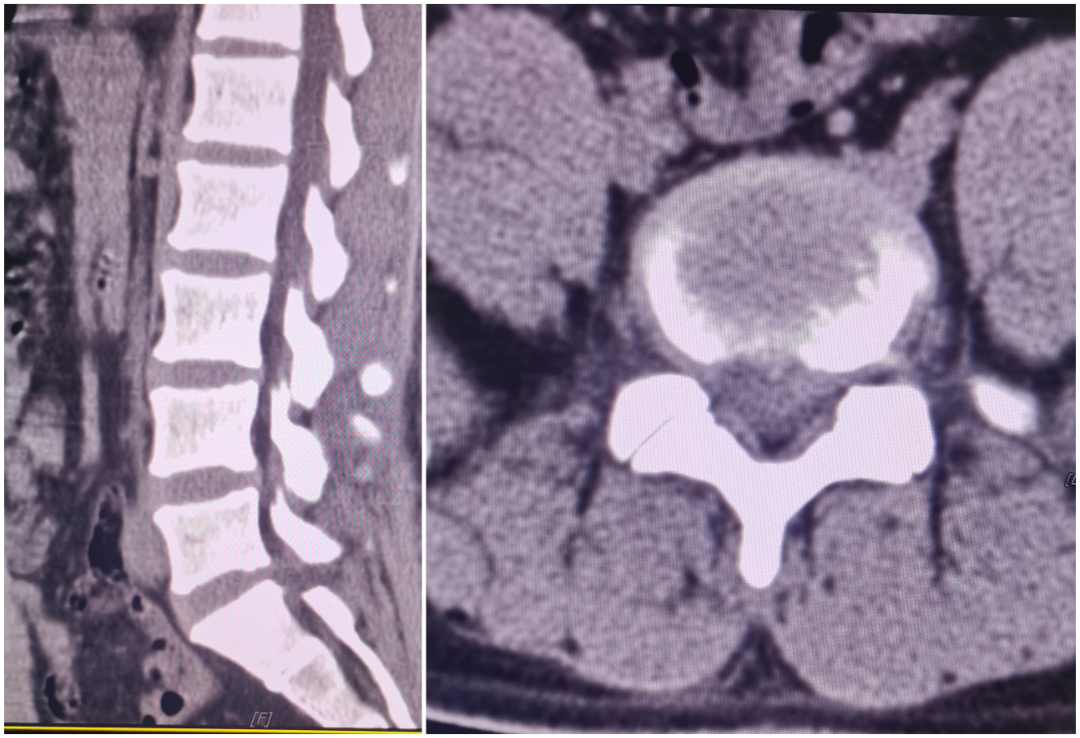

黄某,71岁男性患者,因反复腰部疼痛3年余,再发加重1周入院,查体:脊柱生理弯曲存在,腰部无明显肿胀,未扪及明显台阶感,下腰段椎间隙压痛,椎旁肌稍压痛及叩击痛,双下肢萎缩,右侧直腿抬高试验及加强试验阳性,右足第1趾背伸及跖屈伸肌力减弱,右大腿外侧、小腿外侧、后侧及足背外侧感觉麻木,左下肢感觉正常,结合辅助检查,诊断:腰椎管狭窄症:腰4/5椎间盘突出,于全麻下行经单侧双通道脊柱内镜下腰4/5椎板开窗减压、腰4/5椎间盘摘除、椎间cage植骨融合、经皮钉棒系统内固定术。患者术后腰部及双下肢麻痛症状明显改善。

术前影像学